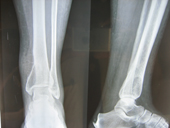

| Fracture Tibia pre op |

Fracture Tibia post op |